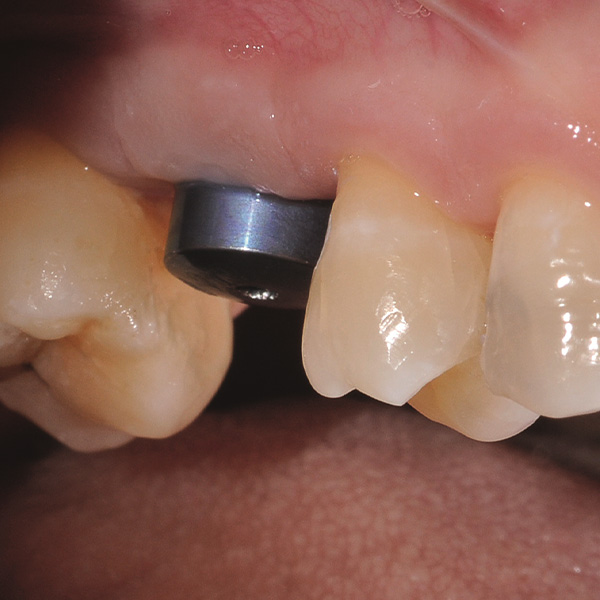

Reconstrucción de corona implantosoportada de cerámica híbrida VITA ENAMIC multiColor

Sobre todo las restauraciones sobre implantes están sometidas a elevadas solicitaciones. Tras la extracción y el implante, al paciente le falta el tejido fibroso elástico del lecho dental natural. En consecuencia, no se absorben las fuerzas oclusales, sino que se transmiten directamente a la restauración, al implante, al hueso y a los dientes antagonistas. La cerámica híbrida VITA ENAMIC incorpora una matriz dual de cerámica (86 % del peso) y polímero (14 % del peso). Esto le otorga una elasticidad similar a la de la dentina y la capacidad de absorber fuerzas oclusales. Gracias a su elevada dimensión vertical, la pieza en bruto policroma VITA ENAMIC multiColor en la geometría EMC-16 posibilita, incluso en caso de hueso atrofiado, la confección de coronas sobre pilar monolíticas de una pieza. El doctor y catedrático Alexander Hassel muestra en el siguiente artículo cómo ha tratado a una paciente empleando este método de restauración.